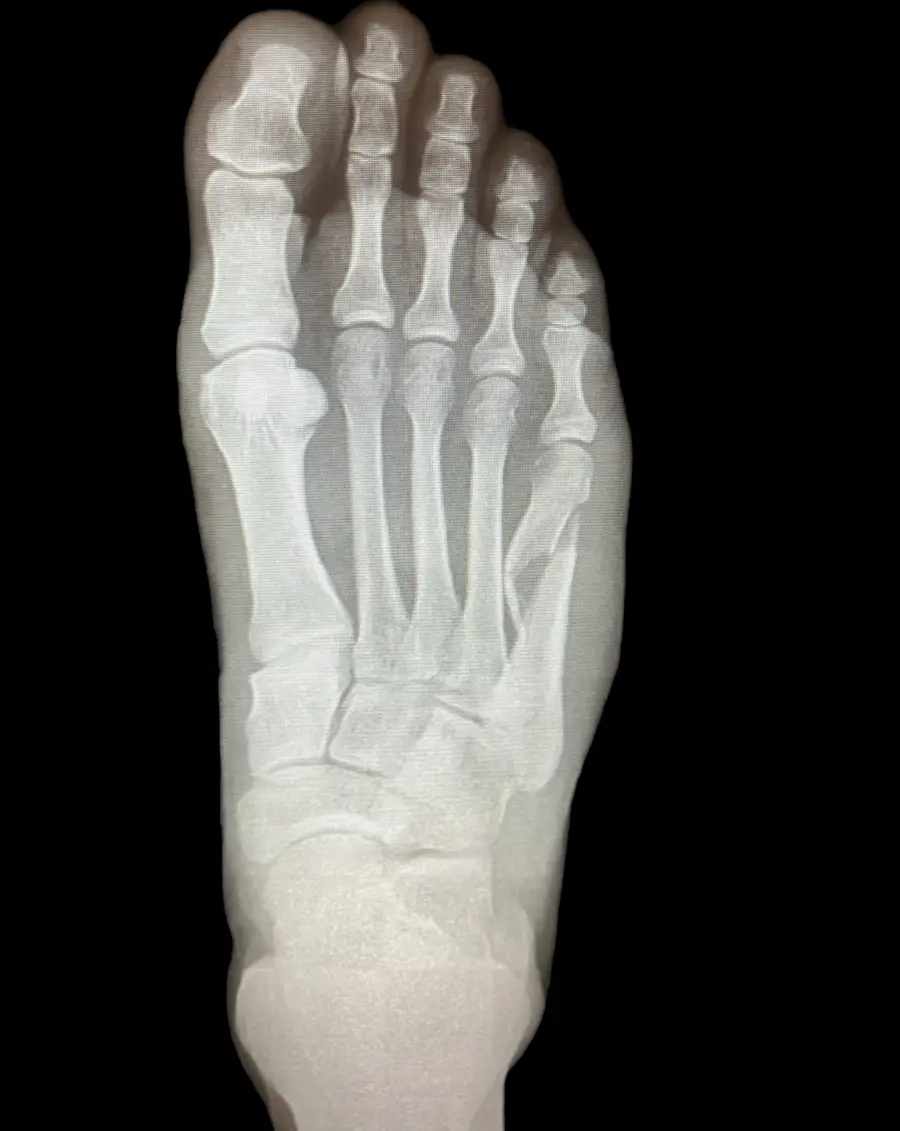

Surgical Intervention at Stepwell Institute is never a “one-size-fits-all” solution. We view surgery as a precise tool used to restore the natural biomechanics of the foot and ankle when non-invasive methods have reached their limit. Our philosophy centers on individualized surgical planning—using advanced imaging to map out the procedure before you ever enter the operating room. From correcting bunions and hammertoes to performing ligament repairs and fracture fixations, Dr. Yakov utilizes techniques designed to minimize trauma to the surrounding tissues, thereby reducing the risk of complications and ensuring a more stable, long-term result for our patients.

Our Case Study